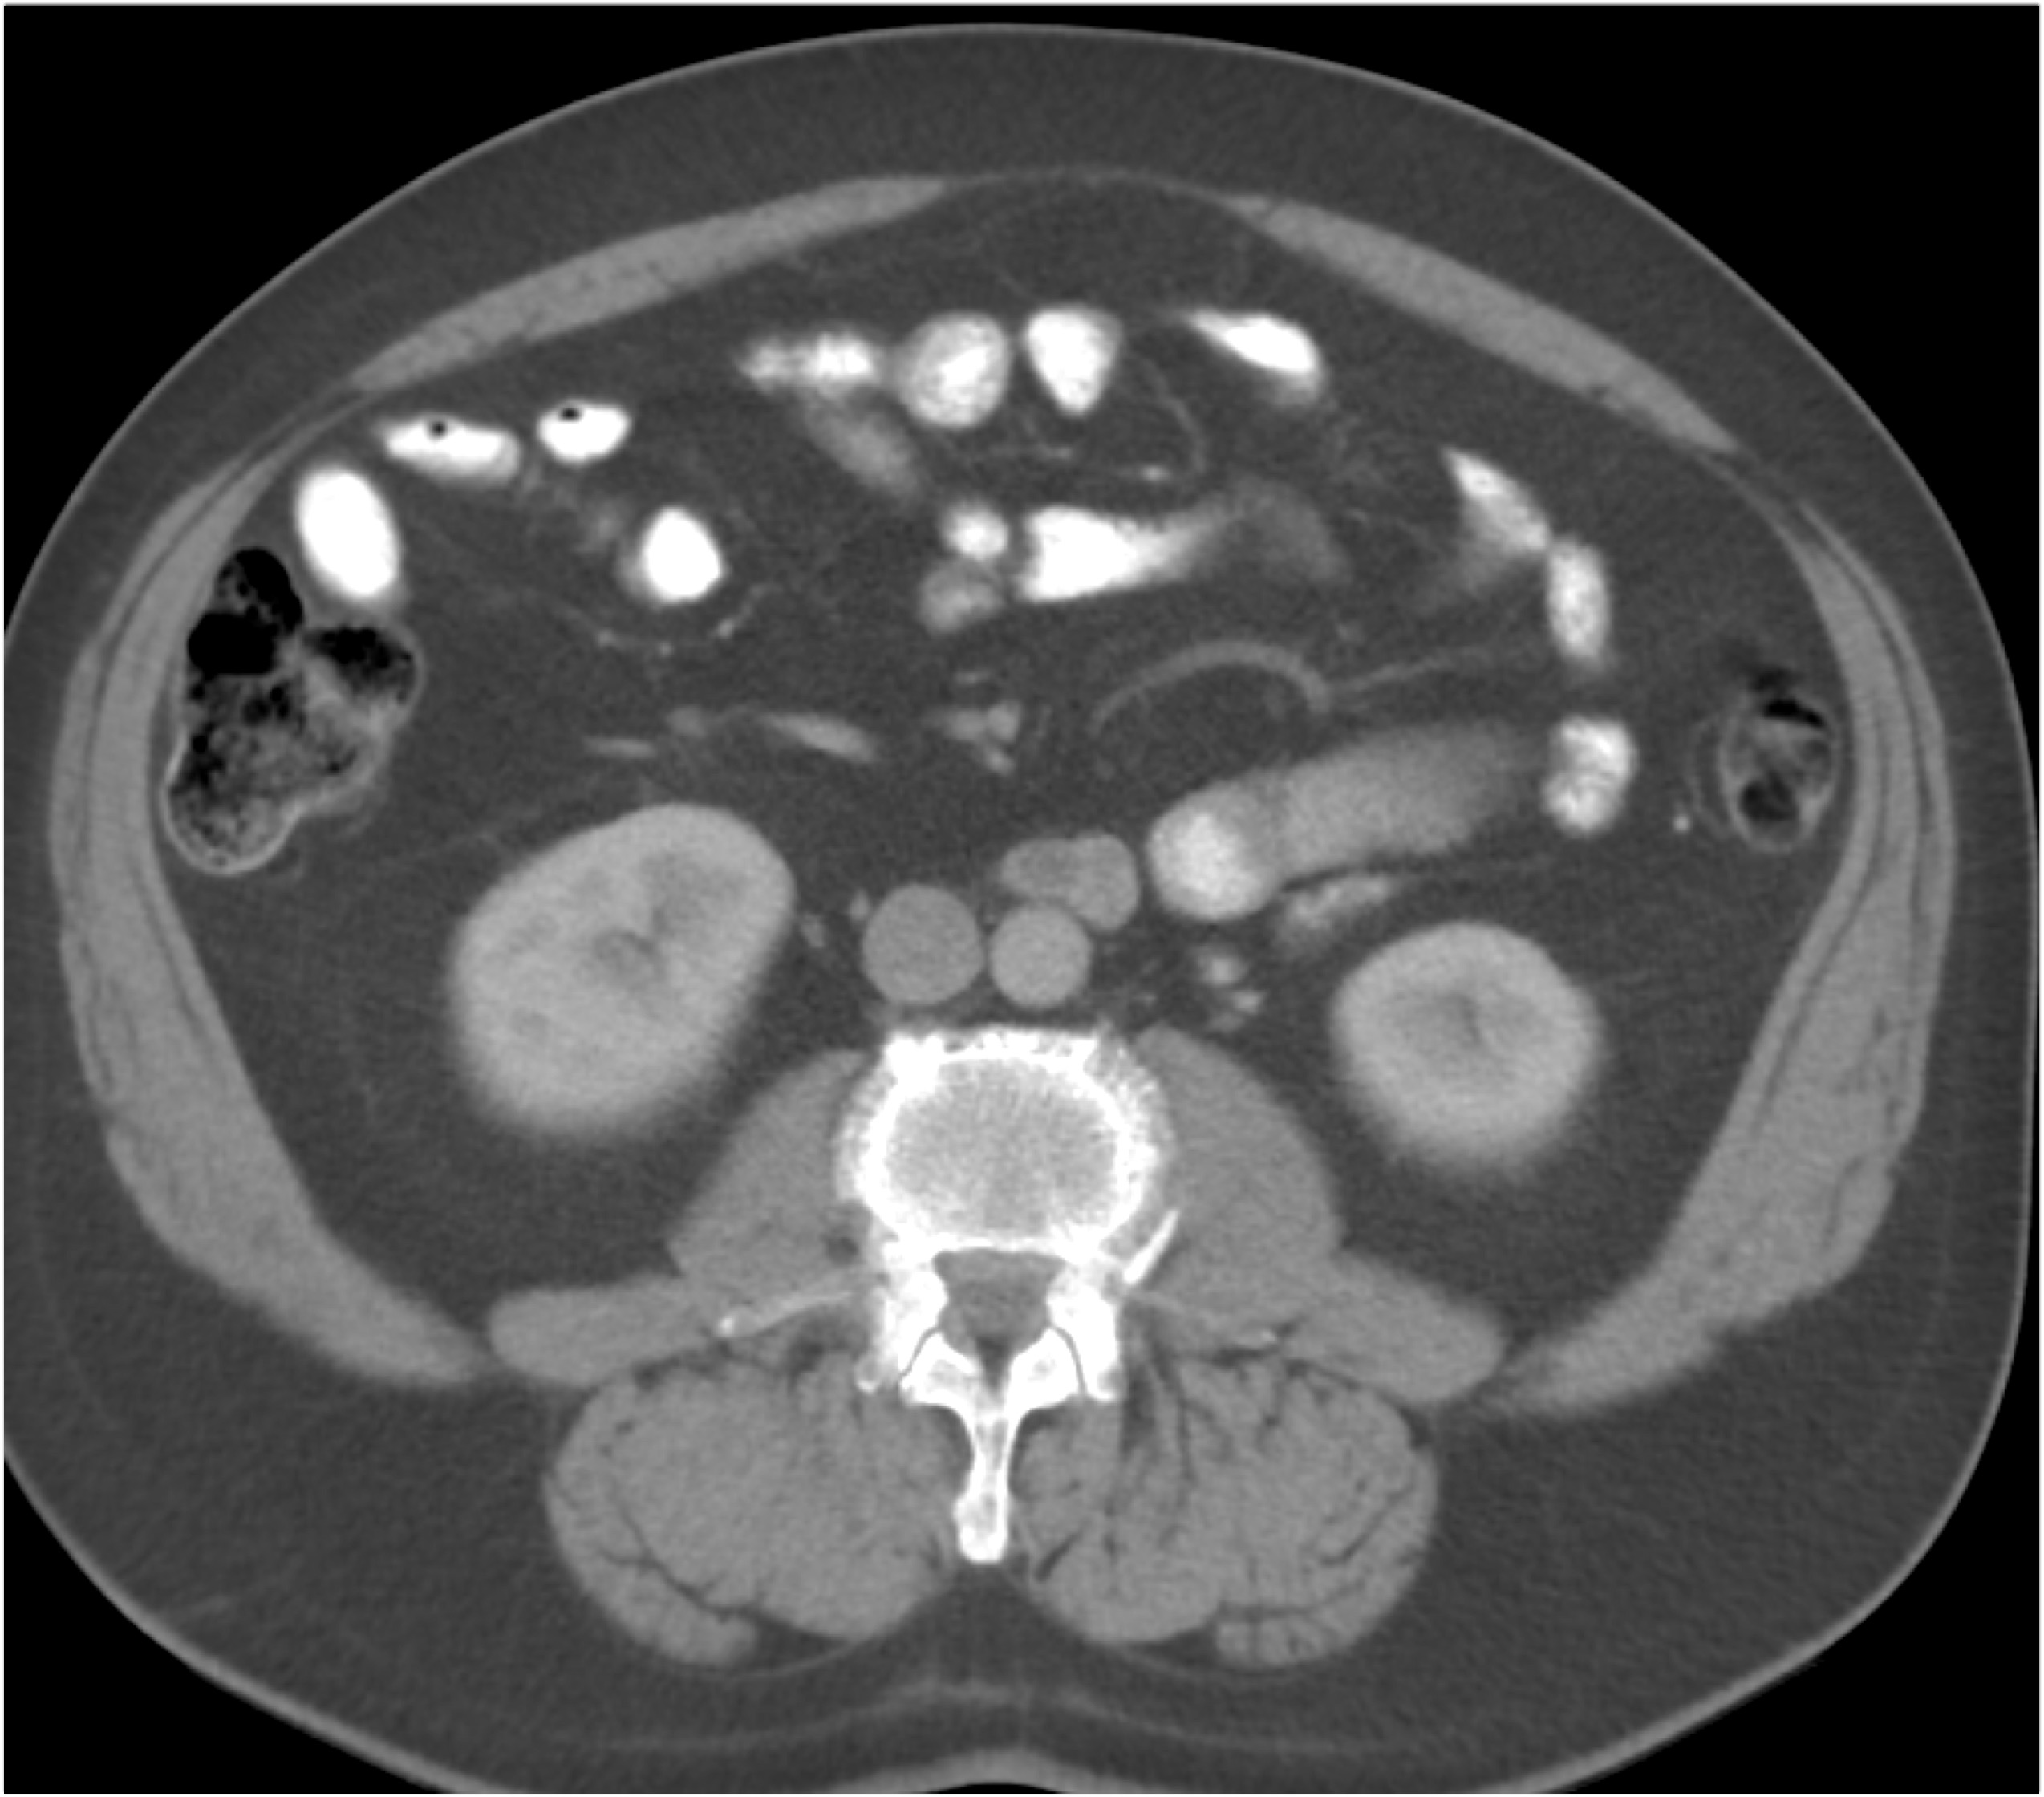

8) The most likely diagnosis for the dominant left renal mass is?

clear cell renal cell carcinoma

metastatic melanoma

papillary renal cell carcinoma

renal oncocytoma